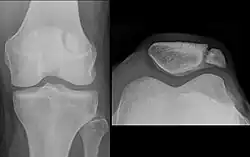

- Die Facies posterior („Hinterfläche“) ist in den oberen zwei Dritteln von hyalinem Gelenkknorpel überzogen, welcher mit etwa 6 mm der dickste Gelenkknorpel im menschlichen Körper ist.[2] Die Facies posterior weist einen vertikalen Grat auf, der sich in den Spalt (Sulcus intercondylaris) zwischen den Condylen (Gelenkknorren) des Oberschenkelknochens einfügt. Er unterteilt die Hinterfläche in zwei Facetten, die wiederum mit den Condylen in Verbindung stehen (artikulieren). Normalerweise beträgt der Winkel zwischen den beiden Facetten 120°–140°.[2] Die laterale (seitliche) Facette ist gewöhnlich deutlich breiter. Je nach Verhältnis der Facetten zueinander werden nach Wiberg und Baumgartl vier Patellaformen unterschieden.[1]